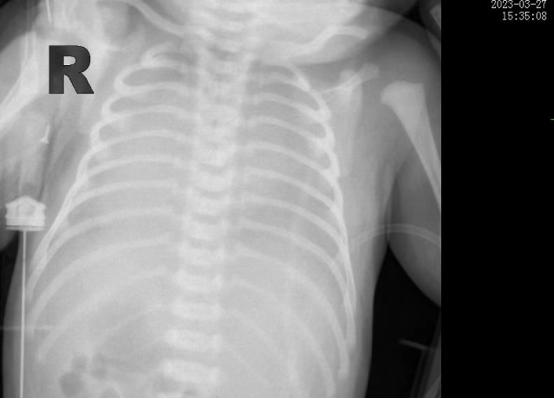

時(shí)間追溯到3月27日,該患兒出生時(shí)哭聲欠連貫,全身可見(jiàn)黃色胎糞附著,羊水三度污染,呼吸稍促,血氧飽和度低,立即轉(zhuǎn)入新生兒科。醫(yī)生立即予以清理呼吸道,常壓給氧,建立靜脈通道后抱入暖箱復(fù)溫,同時(shí)以無(wú)創(chuàng)輔助通氣。然而患兒呼吸窘迫癥狀正在進(jìn)行性加重,胸片提示“白肺”,結(jié)合血?dú)夥治龅葯z查后,患兒被診斷為“急性呼吸窘迫綜合癥”、“呼吸衰竭”。時(shí)間就是生命,主管醫(yī)生張海嬌在與家屬充分溝通同時(shí),副主任醫(yī)師鐘玉芬立即帶領(lǐng)新生兒醫(yī)護(hù)團(tuán)隊(duì)快速采取急救措施,給予患兒氣管插管術(shù)進(jìn)行有創(chuàng)呼吸機(jī)高頻震蕩通氣,并從氣管內(nèi)滴入PS(肺表面活性物質(zhì)),以降低肺泡表面張力,增加肺順應(yīng)性,患兒血氧這才穩(wěn)定下來(lái)。

在科室團(tuán)隊(duì)的共同努力下,患兒歷經(jīng)5天有創(chuàng)通氣5天無(wú)創(chuàng)通氣,再調(diào)整為5天吸氧后已經(jīng)實(shí)現(xiàn)呼吸自由,復(fù)查肺部CT,終于看到白肺已云開(kāi)霧散。4月15日,歷時(shí)17天的醫(yī)療救治,患兒順利出院,回到了媽媽的懷抱。

據(jù)悉,新生兒急性呼吸窘迫綜合征(ARDS)是一種嚴(yán)重威脅新生兒生命的呼吸危重癥,其主要臨床表現(xiàn)為不同程度的低氧血癥,雙肺彌漫性透光度下降,炎性滲出伴肺順應(yīng)性下降。根據(jù)國(guó)際新生兒ARDS多中心研究中期報(bào)告,新生兒ARDS病死率大約為20%,而早期識(shí)別,進(jìn)行良好的肺復(fù)張,預(yù)防及治療肺動(dòng)脈高壓、心臟衰竭、液體管理及積極抗感染等綜合治療以降低病死率。